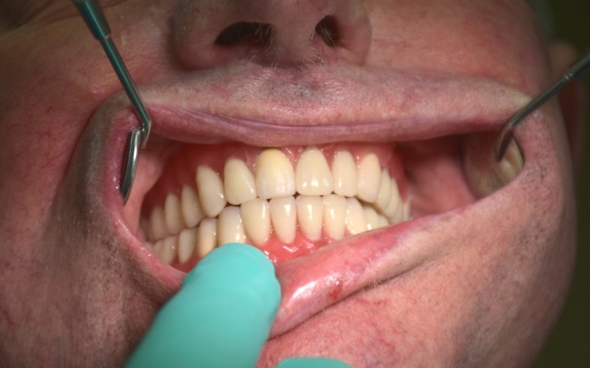

Bilder sagen mehr als Worte - wir zeigen Ihnen, wie aus Lückengebissen und schlechten Zähnen mit exzellenter Zahntechnik ein strahlendes neues Lächeln entsteht.

Metallkeramische Oberkiefer- und Unterkiefer-Vollbrücken

Der 48 jährige österreichische Patient erschien an unserer Zahnklinik zu einem Beratungstermin, wo eine Röntgenaufnahme und ein Kostenplan für metallkeramische Vollbrücken im Ober- und Unterkiefer mit insgesamt 25 Kronen erstellt wurden.

Wie sieht ein fertiger Zahnersatz aus? Schauen Sie sich hier Vorher-Nachher-Bilder an und finden Sie es heraus.